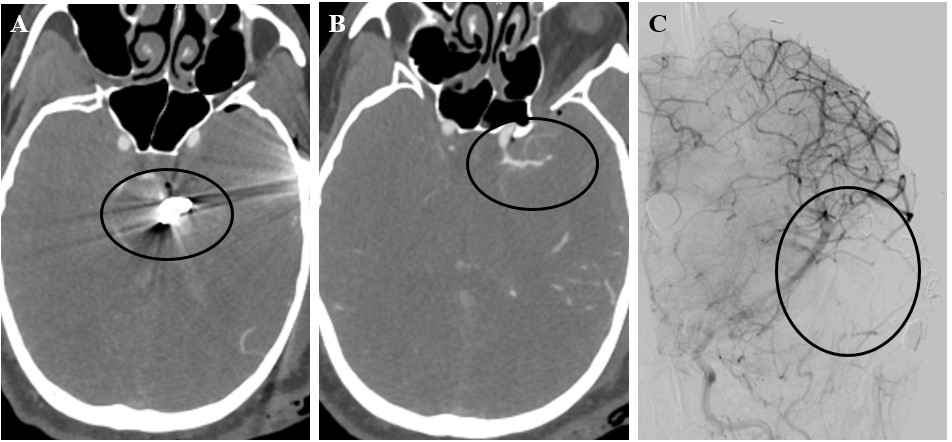

Traumatic intracranial pseudoaneurysms (TICAs) and penetrating cerebrovascular injuries (PCVI) are a frequent complication of gunshot wounds to the head (GSWH)[1]. Their occurrence, mainly due to more sophisticated imaging technologies, including the introduction of computed tomography angiography (CTA) and digital subtraction angiography (DSA), has significantly increased since the first clinical reports in the 1970s [2-4]. Delayed cerebral angiograms from a few days up to several weeks after the initial injury were standard of care in the early series from the Iran-Iraq and the Lebanese Civil wars [5-11]. These provided the first evidence of TICAs secondary to GSWH or shrapnel injury, highlighting their clinical importance and significant mortality (Figure 1).

Choosing Vessel Imaging Modality before Surgical Intervention

In a recent study, Serra et al. suggested that a significant number of patients, up to 20% of those suffering a civilian GSWH, can develop a pseudoaneurysm in the hyper-acute window [14]. This number, despite being significantly higher than previous estimates, does not include other types of vascular injuries [6,9,11,25-27]. Importantly, while this study showed a CTA sensitivity in line with Meyer’s prospective study, it also demonstrated that patients presenting with a TICA had higher chances of developing an intracerebral hematoma [14]. Further, these subjects underwent surgery more often and suffered higher rates of bleed expansion and intraventricular hemorrhage. Another important factor to consider when evaluating new lesions discovered on CTA and not confirmed on DSA is the spontaneous obliteration of pseudoaneurysms, dissections, fistulas. This was again demonstrated by Serra et al. in their series, as nine patients (9/28, ~30%) underwent spontaneous TICA resolution on repeat CTA/DSA. Admission CTA might therefore cast light on the early phases after pTBI, where biological processes might explain part of the difference with DSA. In the future, further characterization with ultra-early DSA might be warranted in these subjects. This will allow to confirm the presence of TICAs and other vascular injuries seen on CTA, address these lesions early via endovascular technique, and provide important data to validate the use of CT in pTBI settings. A clinical trial of ultra-early CTA/DSA may significantly improve our understanding of GSWH pathophysiology, a problem that has become highly relevant in recent years, following the increase in civilian GSWs. CTA, despite the recent advancements in its sensitivity, is still outperformed by DSA in terms of pure sensitivity and specificity. Given its availability it can nonetheless play a pivotal role in the preoperative evaluation of pTBI – TICAs and PCVIs can be quickly identified, and the surgical approach modified to address these lesions. If noticed on admission CTA, TICAs can be trapped and excised or cauterized, reducing blood loss and the risk of subarachnoid hemorrhage (Figures 3 and 4). On the other hand, early DSA allows for direct obliteration of the lesion via Onyx, coils, glue [25,28,29]. While the advantages of treatment during angiography are frequently highlighted and used to justify early DSA, it is evident that in emergent scenarios where immediate decompression and debridement need to be performed, this exam can significantly delay care and affect patient prognosis. Further, open treatment of TICAs and PCVI has been routinely performed for decades, and it should be stressed that CTA streamlines surgical interventions by allowing the treatment of the lesion and cerebral decompression during the same session.

Post-operative DSA shows several truncated distal MCA branches and mass effect from packing. Follow-up DSA on day 10 post-injury failed to demonstrate additional vascular injuries.